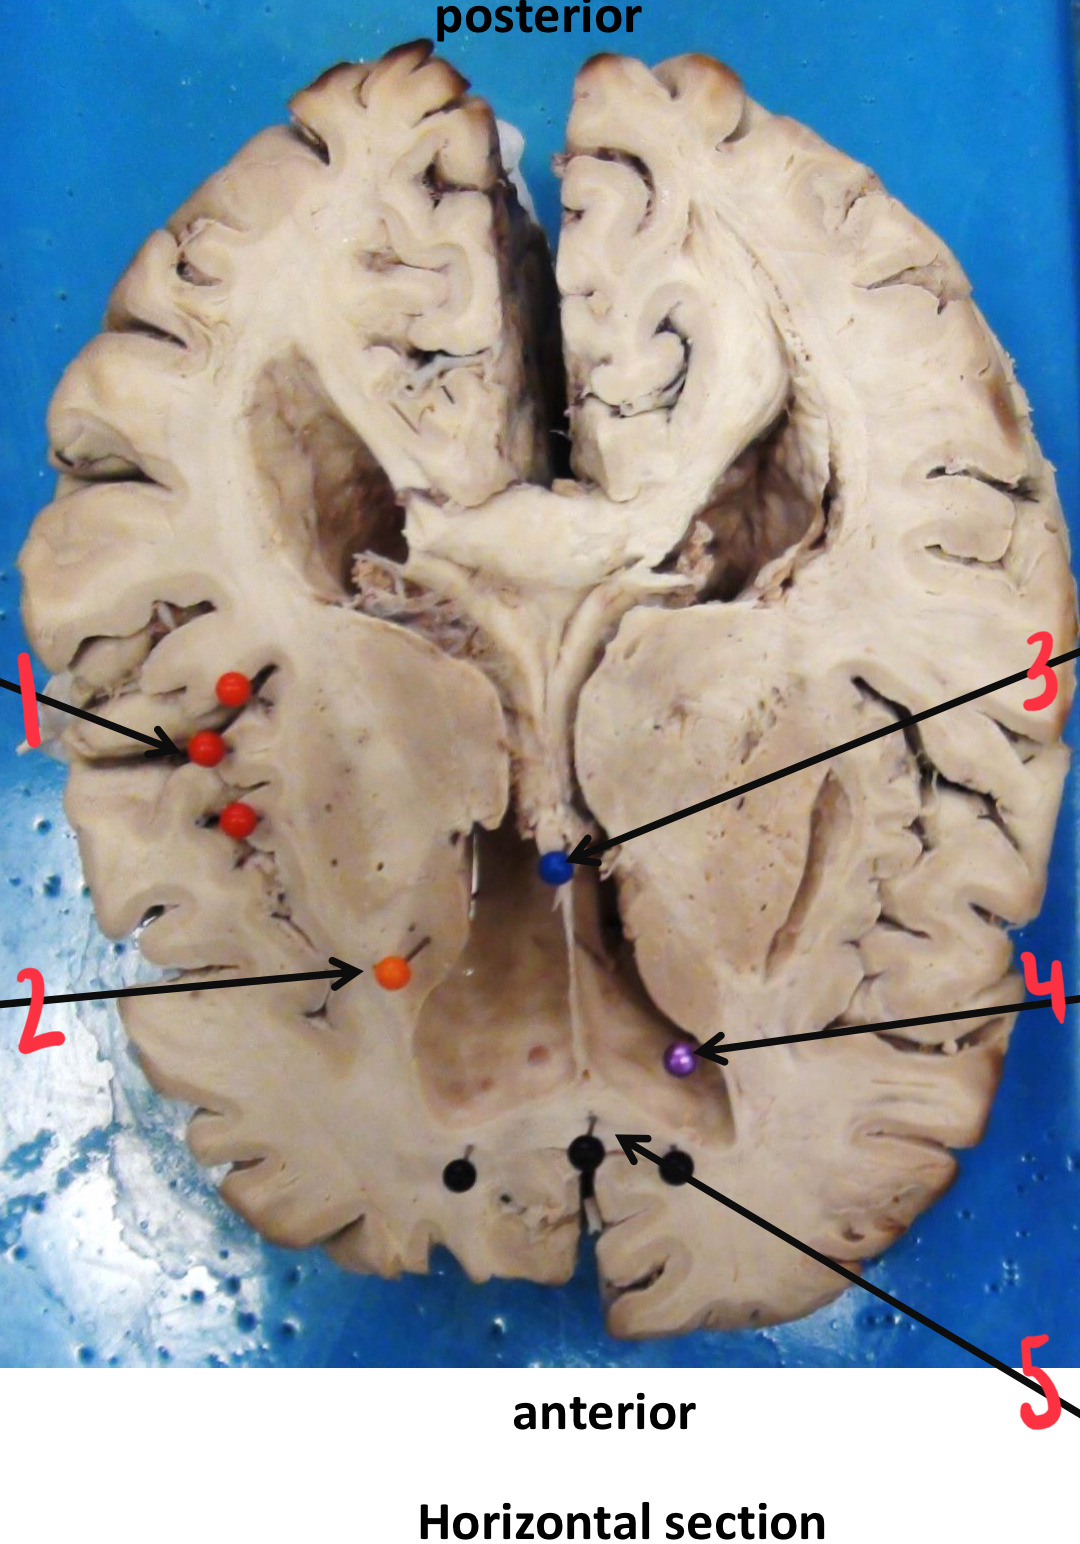

1

corpus callosum

2

caudate nucleus

3

insula (island of Reil)

4

mamillary body